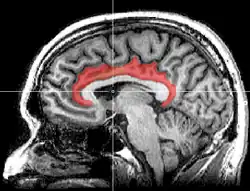

Поясная кора (лат. cortex cingularis) — часть головного мозга, расположенная в медиобазальной части коры больших полушарий. Поясная извилина (лат. gyrus cinguli) является частью поясной коры и расположена непосредственно над мозолистым телом. Поясная кора считается частью лимбической доли.